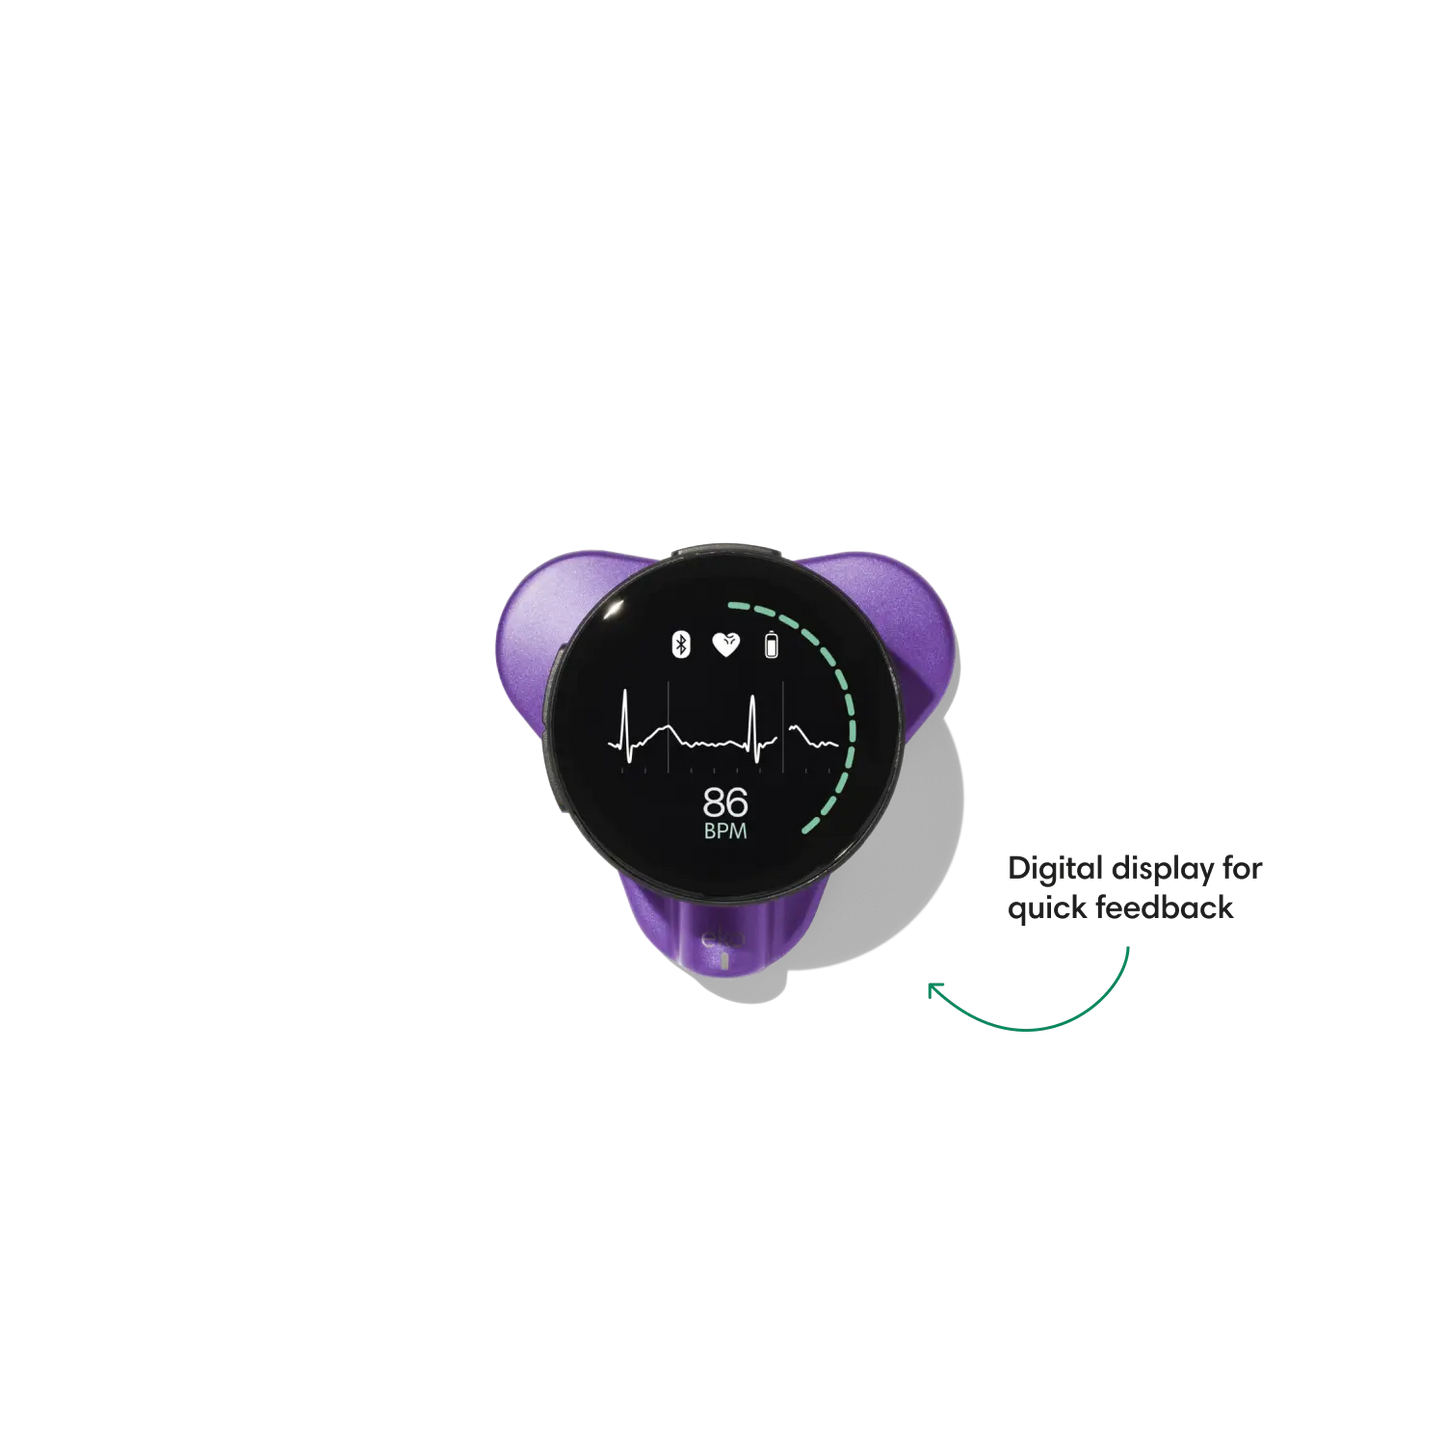

Go beyond sound alone.

For the first time ever, measure heart rate, visualize 3-lead ECG, and see detection results — right on a built-in, full-color display.